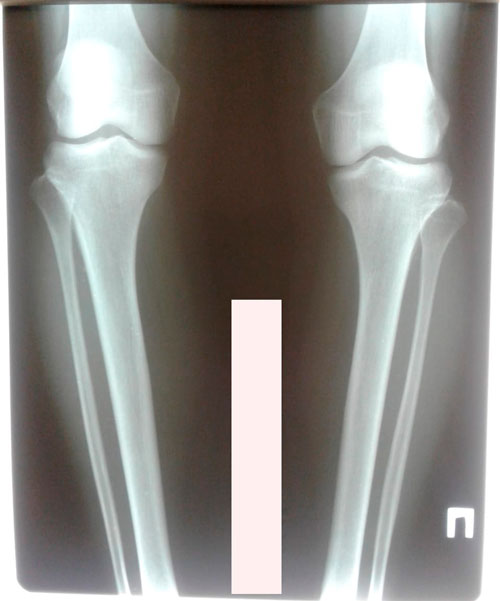

Дата операции - 25.01.2019г.

Дата снятия аппаратов - 24.04.2019г.

Срок сращения - 88 дней.